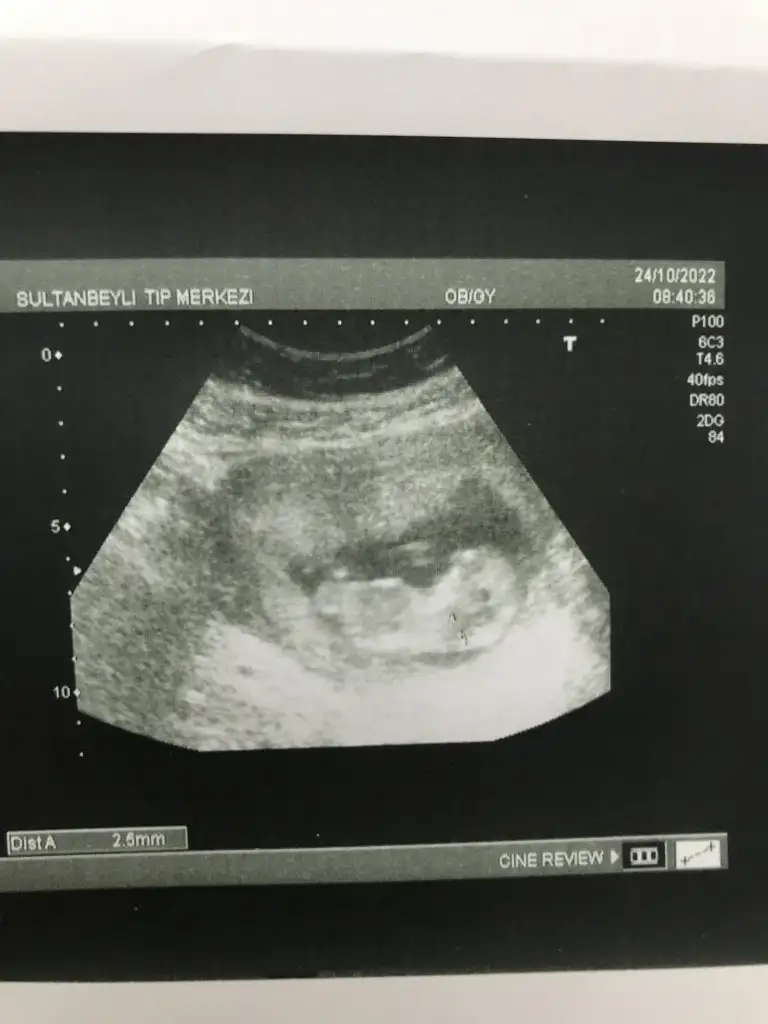

Buda usg lerimSelam Kızlarbir çok kişi gruplardan beni bilir. Yine yetiştim imdatlara

5 ve 14. haftaya kadar olan ultrason fotolarınızı paylaşın. Vajinadan mı yoksa karından mı çekildiğini ve kaç haftalık olduğunu da mutlaka belirtin.